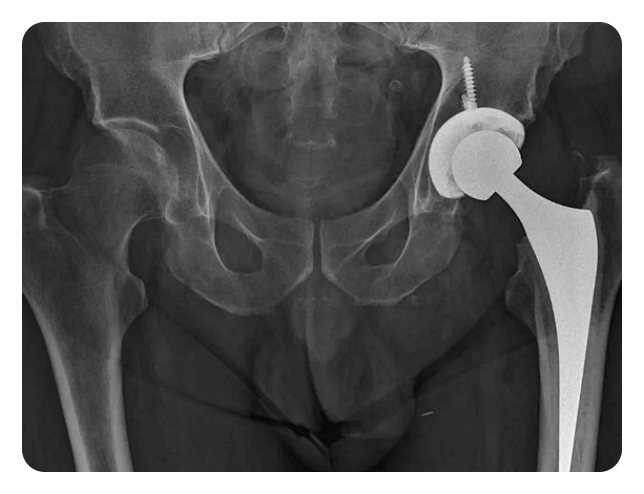

인공관절 치환술: 이 수술은 손상된 관절을 제거하고 그 자리에 인공 관절을 넣는 방식으로 이루어집니다. 인공관절은 대체로 금속, 플라스틱, 혹은 세라믹으로 만들어집니다.

특징: 인공관절 수술은 기본적으로 손상된 고관절을 제거하고 그 자리에 인공관절을 삽입하는 수술입니다. 이 인공관절은 금속, 플라스틱, 혹은 세라믹 등의 재료로 만들어져 있습니다.

뿐만 아니라, X-ray, MRI, CT 등의 영상 진단 검사를 통해 고관절의 상태를 확인하고, 수술의 방향을 결정합니다. 이러한 영상 진단 검사를 통해 관절의 상태를 명확히 파악할 수 있습니다.